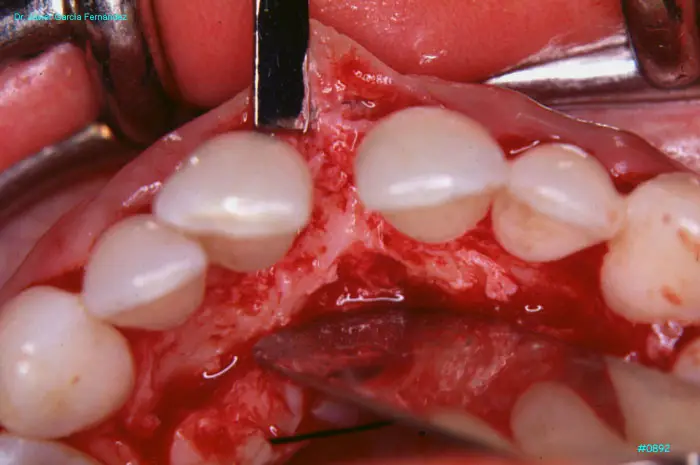

Atlas of Surgical Techniques in Periodontics. Chapter III. Atlas de Técnicas Quirúrgicas en Periodoncia